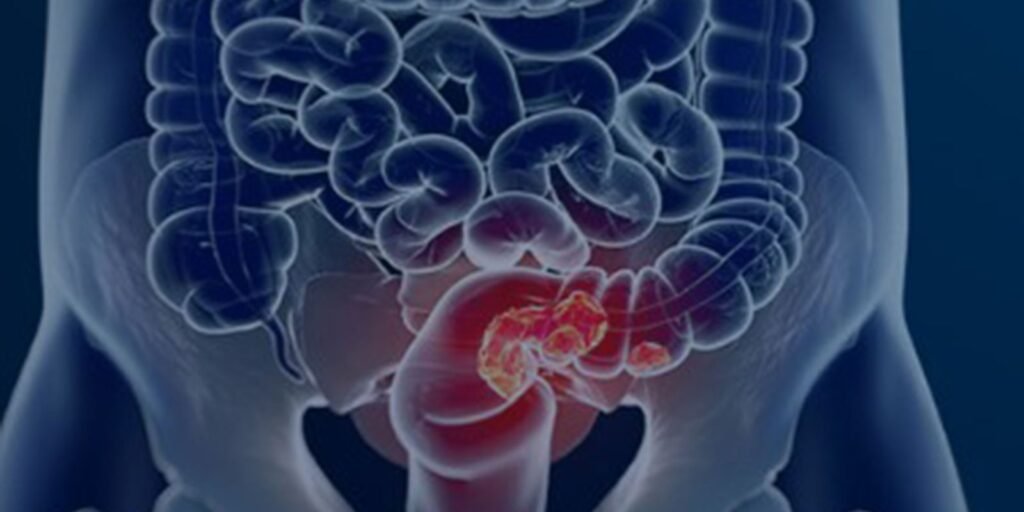

Um estudo recente da Fundação do Câncer revelou um cenário preocupante no Brasil: mais de 60% dos casos de câncer colorretal (CCR) são diagnosticados em estágios avançados. A análise, que abrangeu 177 mil registros hospitalares de câncer entre 2013 e 2022, destaca o impacto devastador do diagnóstico tardio na probabilidade de cura.

De acordo com o diretor-executivo da Fundação do Câncer, o volume de casos de CCR que chegam ao sistema de saúde em estágios avançados é alarmante. Os dados apontam que cerca de 50% dos pacientes são diagnosticados já no estágio 4 (metastático) e outros 25% no estágio 3.

Atualmente, o exame inicial para detecção do CCR no Brasil é a pesquisa de sangue oculto nas fezes, realizada em pessoas acima de 50 anos. Caso o resultado seja positivo, o paciente é encaminhado para colonoscopia. No entanto, a análise de dados sugere que o pico de incidência da doença ocorre entre os 50 e 60 anos, indicando a necessidade de antecipar a idade de rastreamento. A Fundação do Câncer sugere iniciar o rastreamento entre 40 e 45 anos para identificar lesões iniciais e tratá-las antes que evoluam.